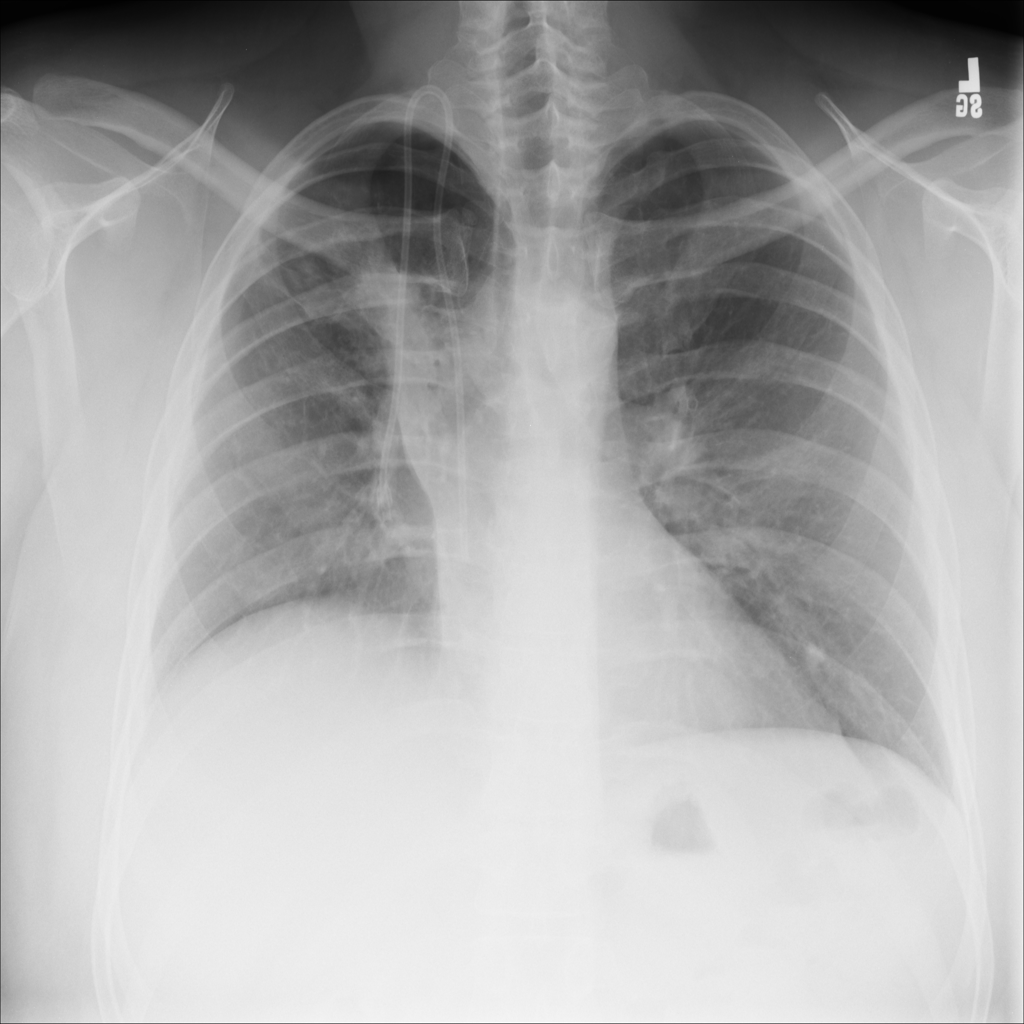

PAT-A1E2 · IMG-001Pneumonia

PAT-A1E2 · IMG-001

AP